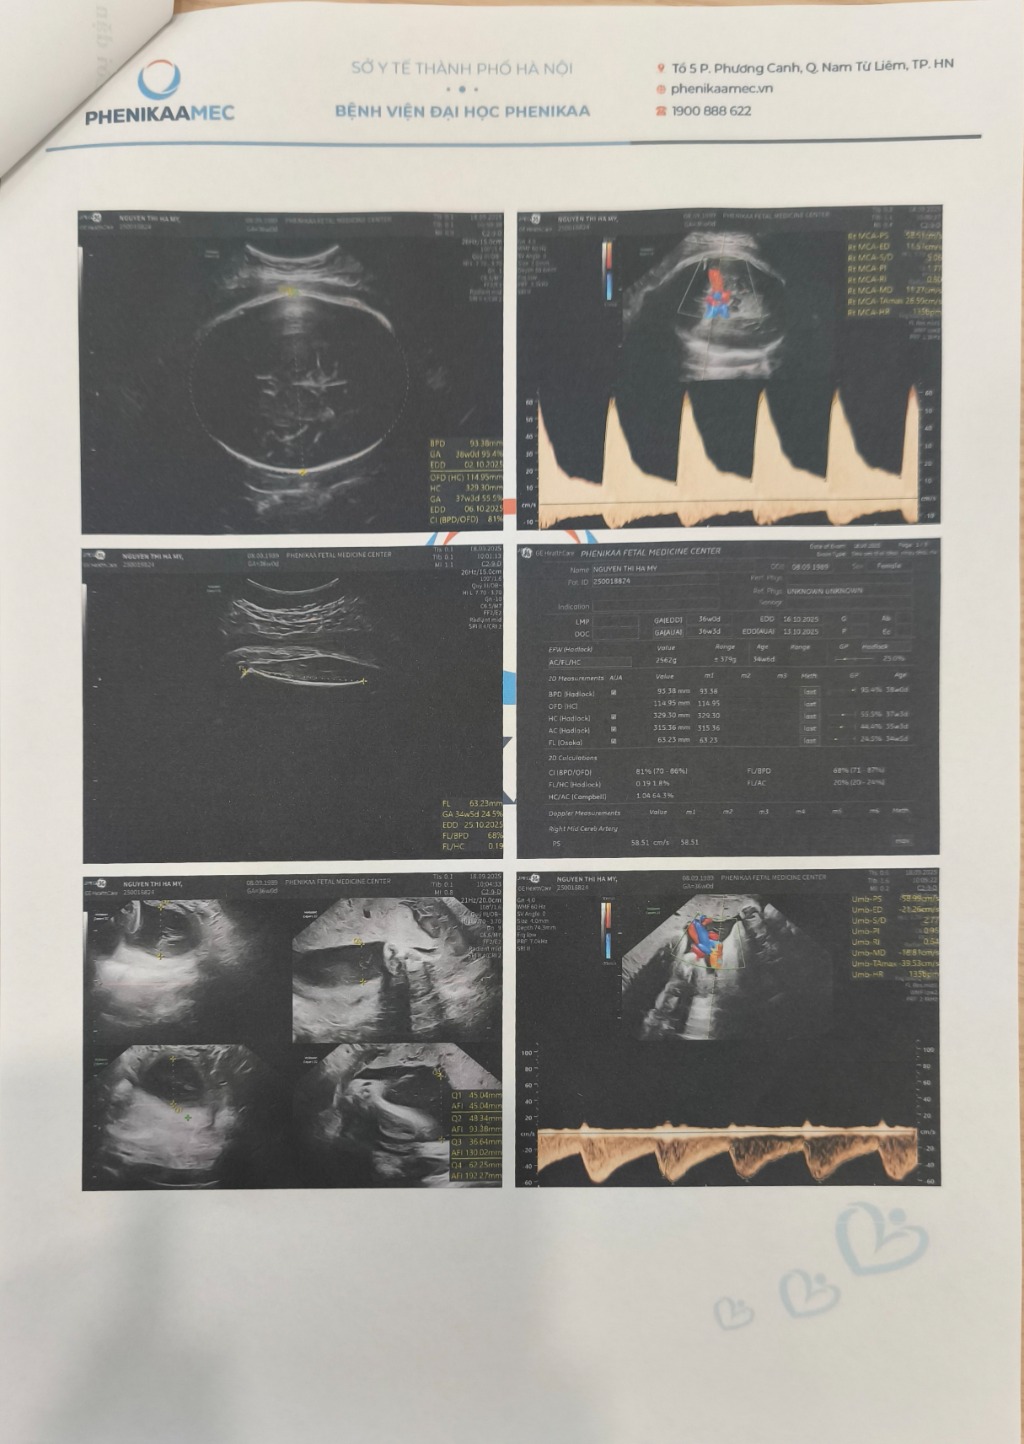

Nguyễn Thị Hà My